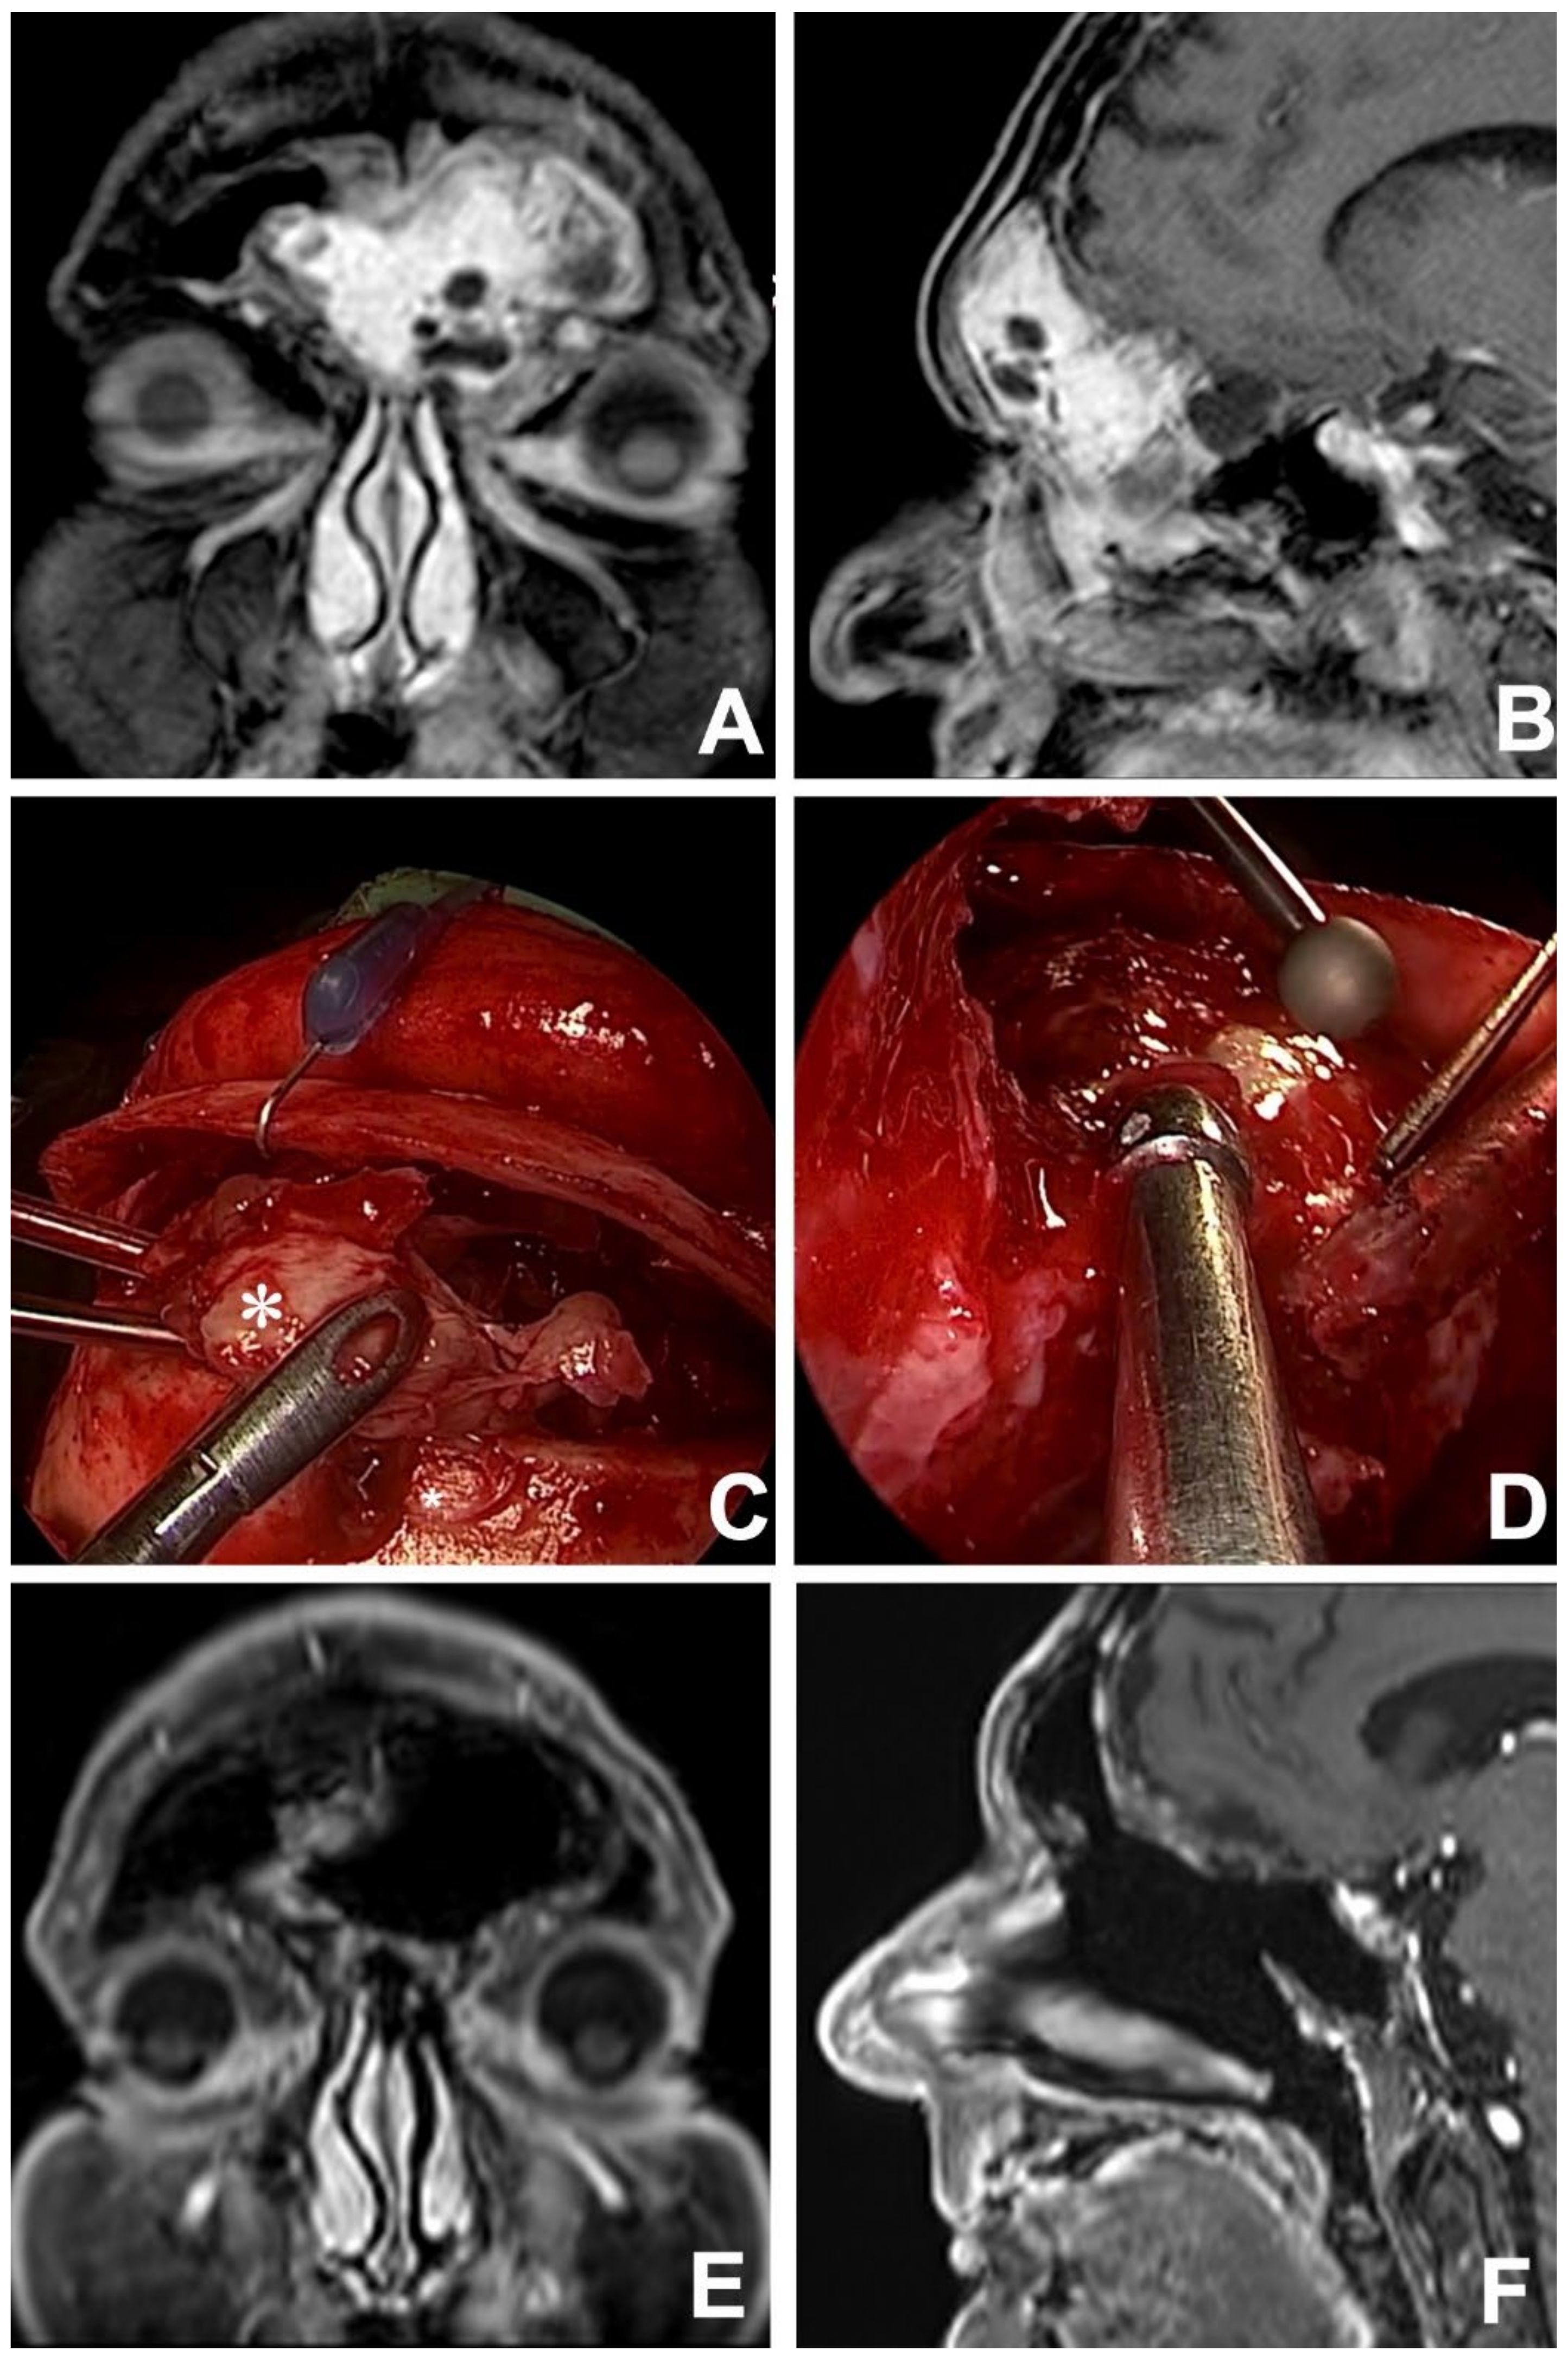

Figure 3.

Contrast-enhanced MRI in coronal (A) and sagittal (B) views showing a left frontoethmoidal INI-1 deficient squamous cell carcinoma. After 3 cycles of induction chemotherapy (TPF regimen) an MRI in the coronal (C) and axial (D) view revealed an incomplete response. Tumor persistence was resected via a combined approach: endoscopic transnasal and osteoplastic flap (E), with an exposition of anterior cranial fossa dura (*) which appeared to be free from tumor infiltration (F). At 12 months, postoperative contrast-enhanced MRI in coronal (G) and axial (H) views revealed no local recurrence.

Among rhinologists, the frontal sinus is recognized to be one the most challenging areas to reach surgically and, even nowadays, external approaches might be needed to manage specific situations (Figure 4) [62]. Over the years, instrumental and technological evolutions have allowed the application of minimally-invasive endoscopic approaches in the management of frontal disease, even in the case of malignant tumors. Currently, endoscopic transnasal and external approaches (i.e., transcranial/transfacial) should be considered as complementary techniques that must be mastered by the skull base surgeon, who must be able to switch from endonasal to external procedures whenever required, depending on intraoperative findings (Figure 5).

Preoperative MRI in coronal (A) and sagittal (B) views showing a frontoethmoidal neoplasm with massive bilateral frontal sinus involvement. After an endoscopic transnasal biopsy, the lesion was histologically defined as biphenotypic sinonasal sarcoma. The lesion (*) was resected via a combined surgical approach: frontal sinus osteoplastic flap (C) and endoscopic transnasal approach (D), achieving free resection margins. A contrast-enhanced coronal (E) and sagittal (F) MRI performed 2 years after treatment proved no evidence of residual disease and ruled out local recurrences.